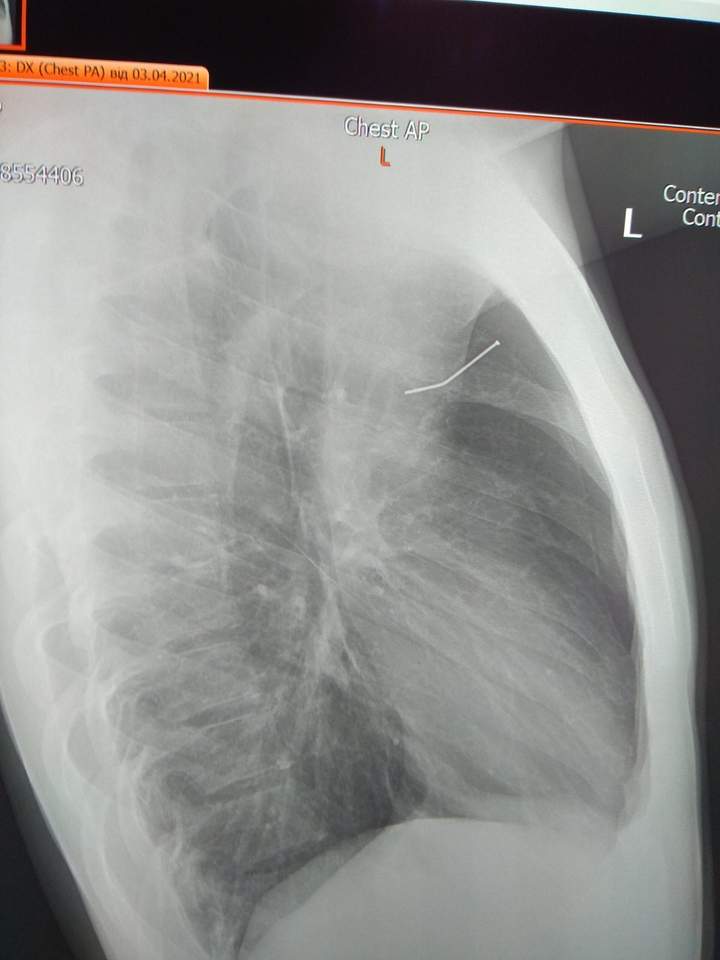

Львівські лікарі витягли з легені неповнолітнього будівельний цвях. 17-річний хлопець випадково пробив орган цвяхозабивним пістолетом. Небезпечний предмет медики дістали без жодних розрізів.

У суботу, 3 квітня, 17-річний хлопець прибивав вдома на Жовківщині дощечки. Коли вже закінчив роботу, перечепився і впав. Внаслідок різкого руху, пневматичний пістолет, який «стріляє» цвяхами, випадково вистрелив йому у груди. Нещасного "швидкою" доставили до львівської обласної дитячої лікарні ОХМАТДИТ, пише Zaxid.net.

Стан хлопця був важкий через дихальну недостатність, у нього була задишка, біль у лівій половині грудної клітки, розвинувся лівобічний пневмоторакс – повітря потрапило у грудну клітку, здавило ліву легеню і зміщувало серце вправо. Хлопця відразу взяли в операційну.

«Ситуація була дуже небезпечна, до аорти бракувало всього кілька міліметрів. Якби цвях пробив аорту, ми б його уже не встигли врятувати, зважаючи, що доїхати з району до Львова так швидко неможливо. Але цьому хлопцю буквально пощастило – цвях пробив легеню. Ми мали ще час на порятунок», – розповів дитячий хірург Микола Микита.

За словами торакального хірурга лікарні Олега Леніва, під час оперативного втручання хірурги застосували найновішу сучасну методику лікування – торакоскопію. Тобто, дістали цвях без жодних розрізів.

Нині пацієнту вже значно краще. Сьогодні йому знімуть один дренаж, а за кілька днів – ще один.